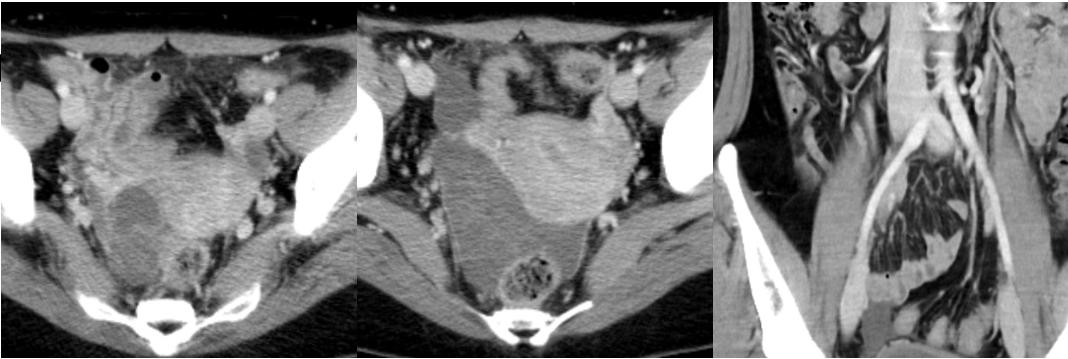

No. 153 症例3:30歳代女性

【画像所見】

CT:

両側卵巣に嚢胞構造

骨盤底部に腹水+軽度腹膜肥厚、腹水の一部がもやもやしている

虫垂の腫大はない